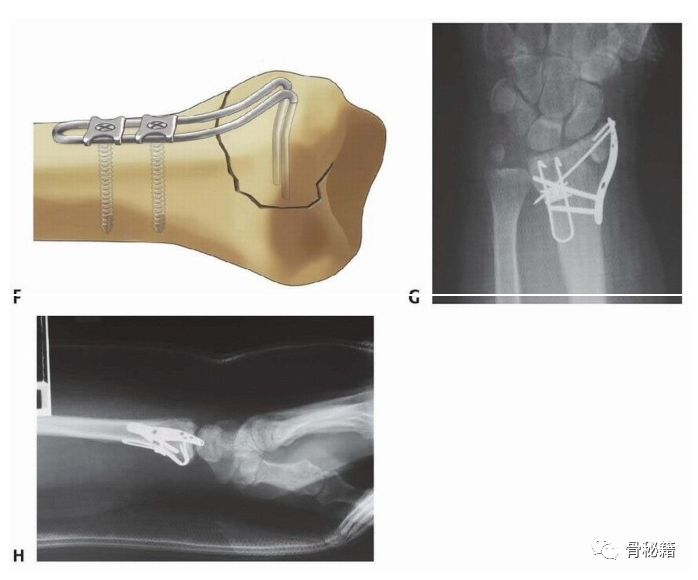

介绍几种可以应用的固定方式,掌侧支持克氏针和及远端的勾钢板。

掌侧勾钢板固定骨折块

还有一些相应的内固定设计,专门诊断此类边缘骨折